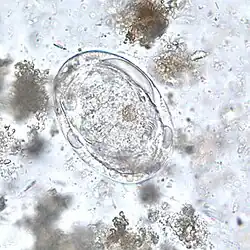

Schistosoma japonicum é um verme achatado parasita, pertencente do filo Platyhelminthes, classe Trematoda. É um importante parasita e um dos principais agente causadores de esquistossomose. Este parasita tem um largo espectro de hospedeiros, infectado pelo menos 31 espécies de mamíferos selvagens, incluindo 9 carnívoros, 16 roedores, um primata, dois insectívoros e três artiodáctilos. Pode ser considerada uma zoonose.[1]

Em resumo, os ovos do parasita são libertados nas fezes e se entram em contacto com água, eles dão origem a larvas de vida livre. A larva tem que infectar o caracol da espécie Oncomelaria hupensis num período de um ou dois dias. Dentro do caracol, a larva passa por reprodução assexuada, através de vários estágios. Depois deste período de reprodução, o caracol terá que infectar um hospedeiro vertebrado com as características mais apropriadas. Assim que a larva cercária penetra a pele do hospedeiro, ela perde a sua cauda e começa a migrar pelo sistema circulatório até às veias mesentéricas, lugar onde se reproduze e efectua a postura dos ovos. Cada par deposita entre 1500 e 3500 ovos por dia nos vasos da parede intestinal. os ovos infiltram-se através dos tecidos e acabam novamente nas fezes.